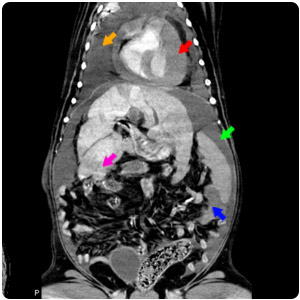

| 背部腫塊、膽囊結石 |

胸腔積液(黃)、心包囊積液(紅)、

肝腫大伴有不均質影像(紫)、腹水(綠)、

脾腫塊(藍) |

| Hernia |

脊椎旁腫塊(黃)、脾腫塊(紅) |